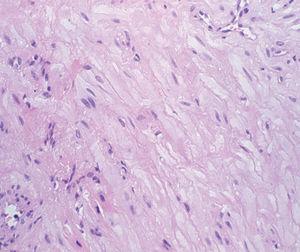

La exploración física mostraba un nódulo (fig. 1) de un diámetro aproximado de 8 x 10 mm, de color eritematoparduzco, de consistencia blanda a la palpación, localizado en el pliegue formado entre el hélix y el antehélix del pabellón auricular izquierdo. No se palpaban adenopatías locorregionales ni existía ninguna otra lesión cutánea significativa.

Fig. 1.--Nódulo asintomático en el pabellón auricular.